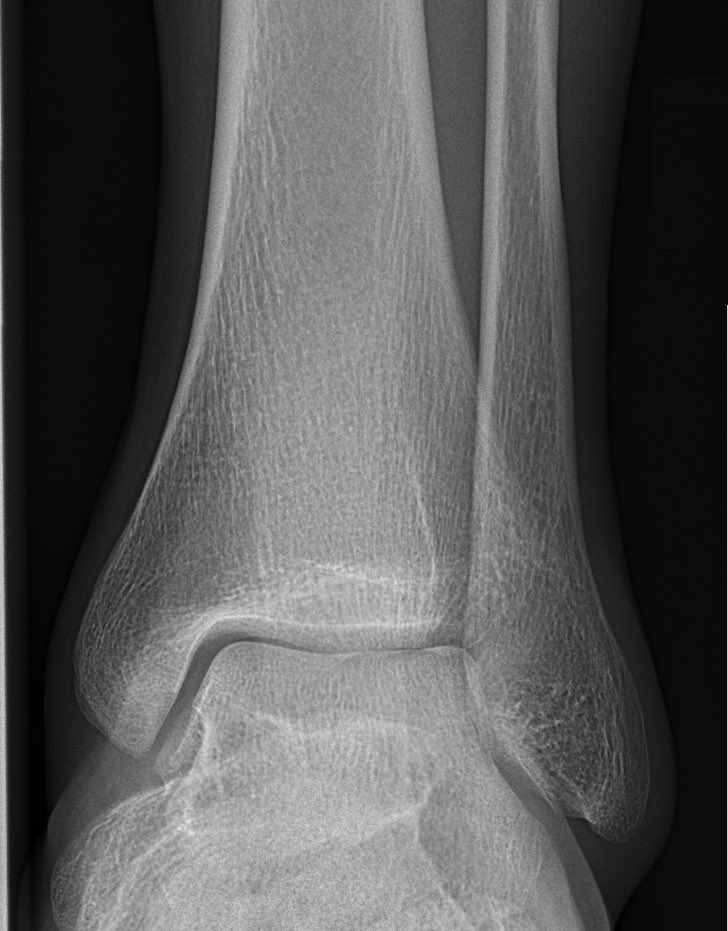

🟡 التواء الكاحل ..

جواب لأغلب التساؤولات فيما يتعلق باصابة أربطة الكاحل الخارجية التي تشكل مايقارب ٩٠٪ من إصابات الكاحل.

هل تحتاج لعمل اشعة اكس ؟

🔵 في الغالب اذا كان المصاب يستطيع المشي ، بدون آلام فلا يحتاج الى الاشعة.

🔵 ولا نلجأ الى الرنين المغناطيسي إلا في حال استمرار الألم لأكثر من ٦-٨ أسابيع.